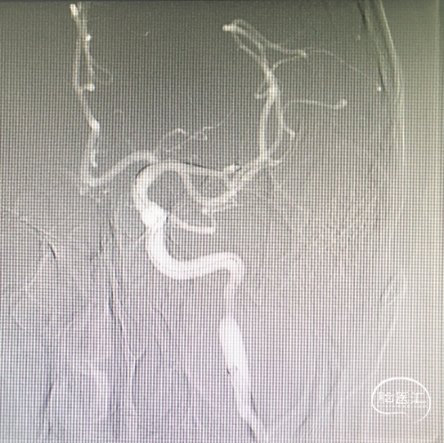

血管再通后,保护伞下,5mm×30mm球囊扩张后,颈内动脉C1段狭窄处置入9×40mm支架。

造影提示左侧颈内动脉系统再通,C1段狭窄处支架成型良好。

患者额颞区梗死灶,病人右侧肢体4级出院。